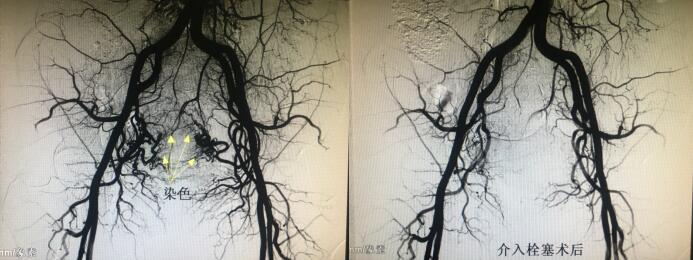

经人介绍来到MILAN.COM介入科,经李建国主任术前评估,患者无介入手术禁忌症,于4月16日早9点行介入手术。术中采用右肱动脉穿刺、超选择双侧子宫动脉造影栓塞术,手术顺利历时约40分钟,成功保全了子宫。术后患者步入病房,避免了因卧床制动而形成下肢深静脉血栓的风险...